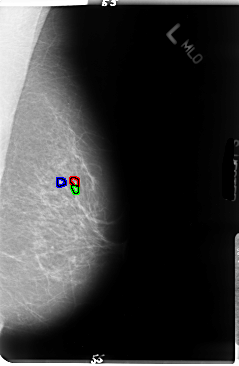

Digital Database for Screening Mammography

Volume: cancer_01 Case: B-3045-1

B_3045_1.LEFT_MLO

LEFT_MLO LINES 4752 PIXELS_PER_LINE 3096 BITS_PER_PIXEL 12 RESOLUTION 50 OVERLAY

FILE: B_3045_1.LEFT_MLO.OVERLAY

TOTAL_ABNORMALITIES 3

ABNORMALITY 1

LESION_TYPE CALCIFICATION TYPE FINE_LINEAR_BRANCHING DISTRIBUTION CLUSTERED-LINEAR

ASSESSMENT 4

SUBTLETY 3

PATHOLOGY MALIGNANT

ABNORMALITY 2

ABNORMALITY 3